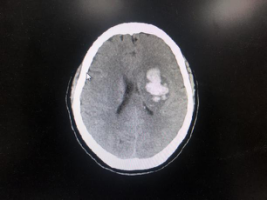

患者头颅CT示可见左侧基底节区团块状高密度出血灶,左侧侧脑室受压变窄。